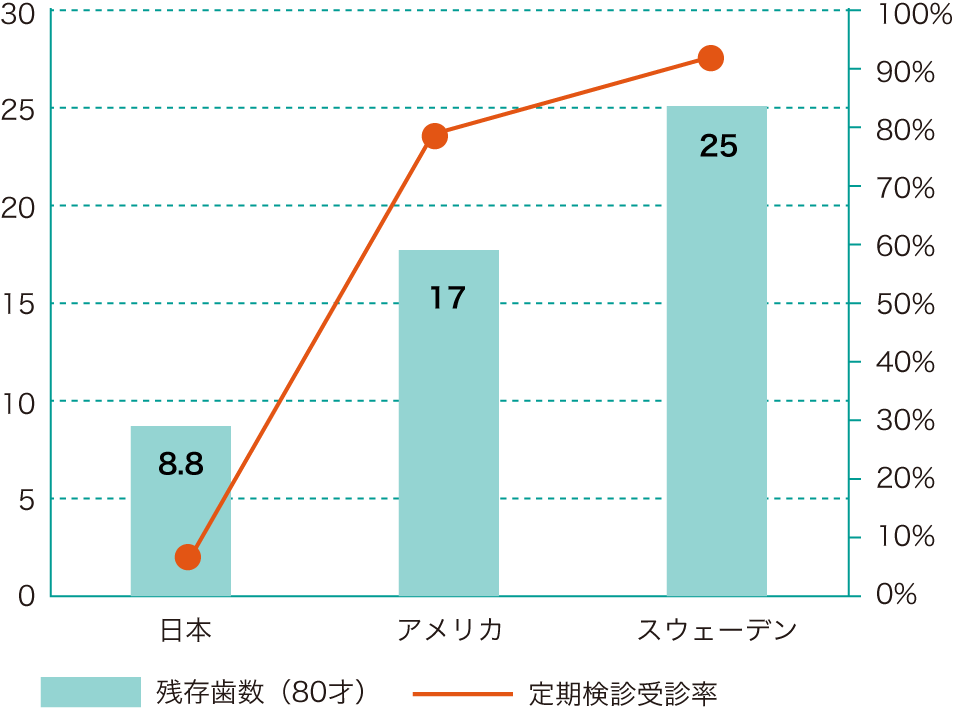

8020運動って?

■80歳で20本の歯を残しましょう。

■歯が20本以下になると健康な食生活ができなくなります。

■長寿世界トップの日本ですが、80歳で平均10本。

■80歳で20本以上の歯が残っている人の割合が21%と低い値です。

■スウェーデンでは80歳で平均20本以上!

■日本の定期健診の受診率はわずか2%。

■歯の長寿国スウェーデンでは大人の定期検診受診率は80%以上、子供は100%です。